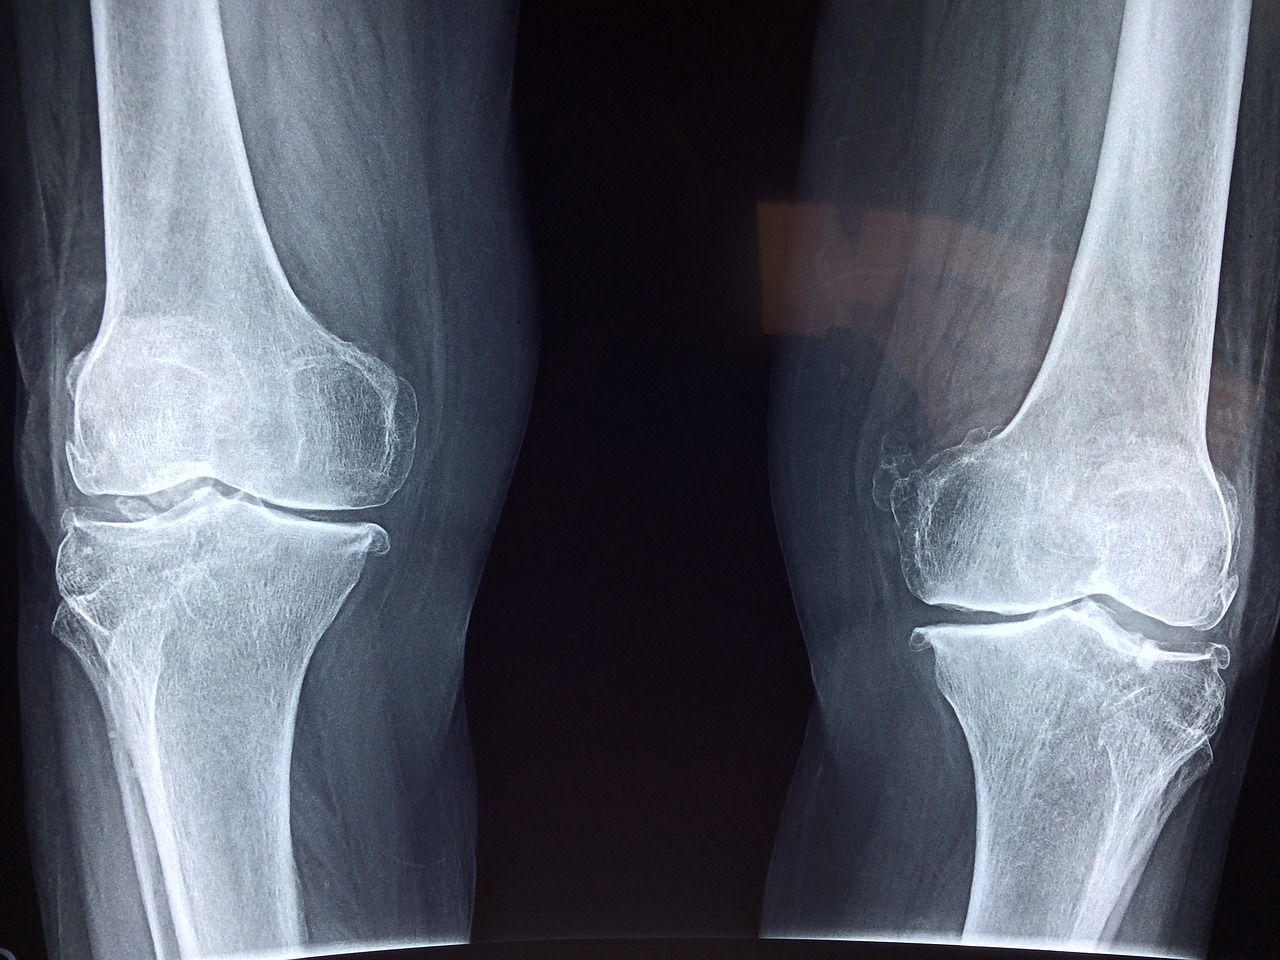

무릎 통증으로 일상생활에 어려움을 겪는 저소득층 어르신들을 위해, 정부는 무릎인공관절 수술 지원사업을 시행하고 있습니다. 이 사업은 수술비 부담을 덜어드려 건강한 삶을 영위할 수 있도록 돕는 제도입니다. 아래에서 수술 대상, 지원 금액, 신청 방법 등을 자세히 안내해 드리겠습니다.

- 질환 요건: 건강보험급여 '인공관절치환술(슬관절)' 인정 기준에 준하는 질환자